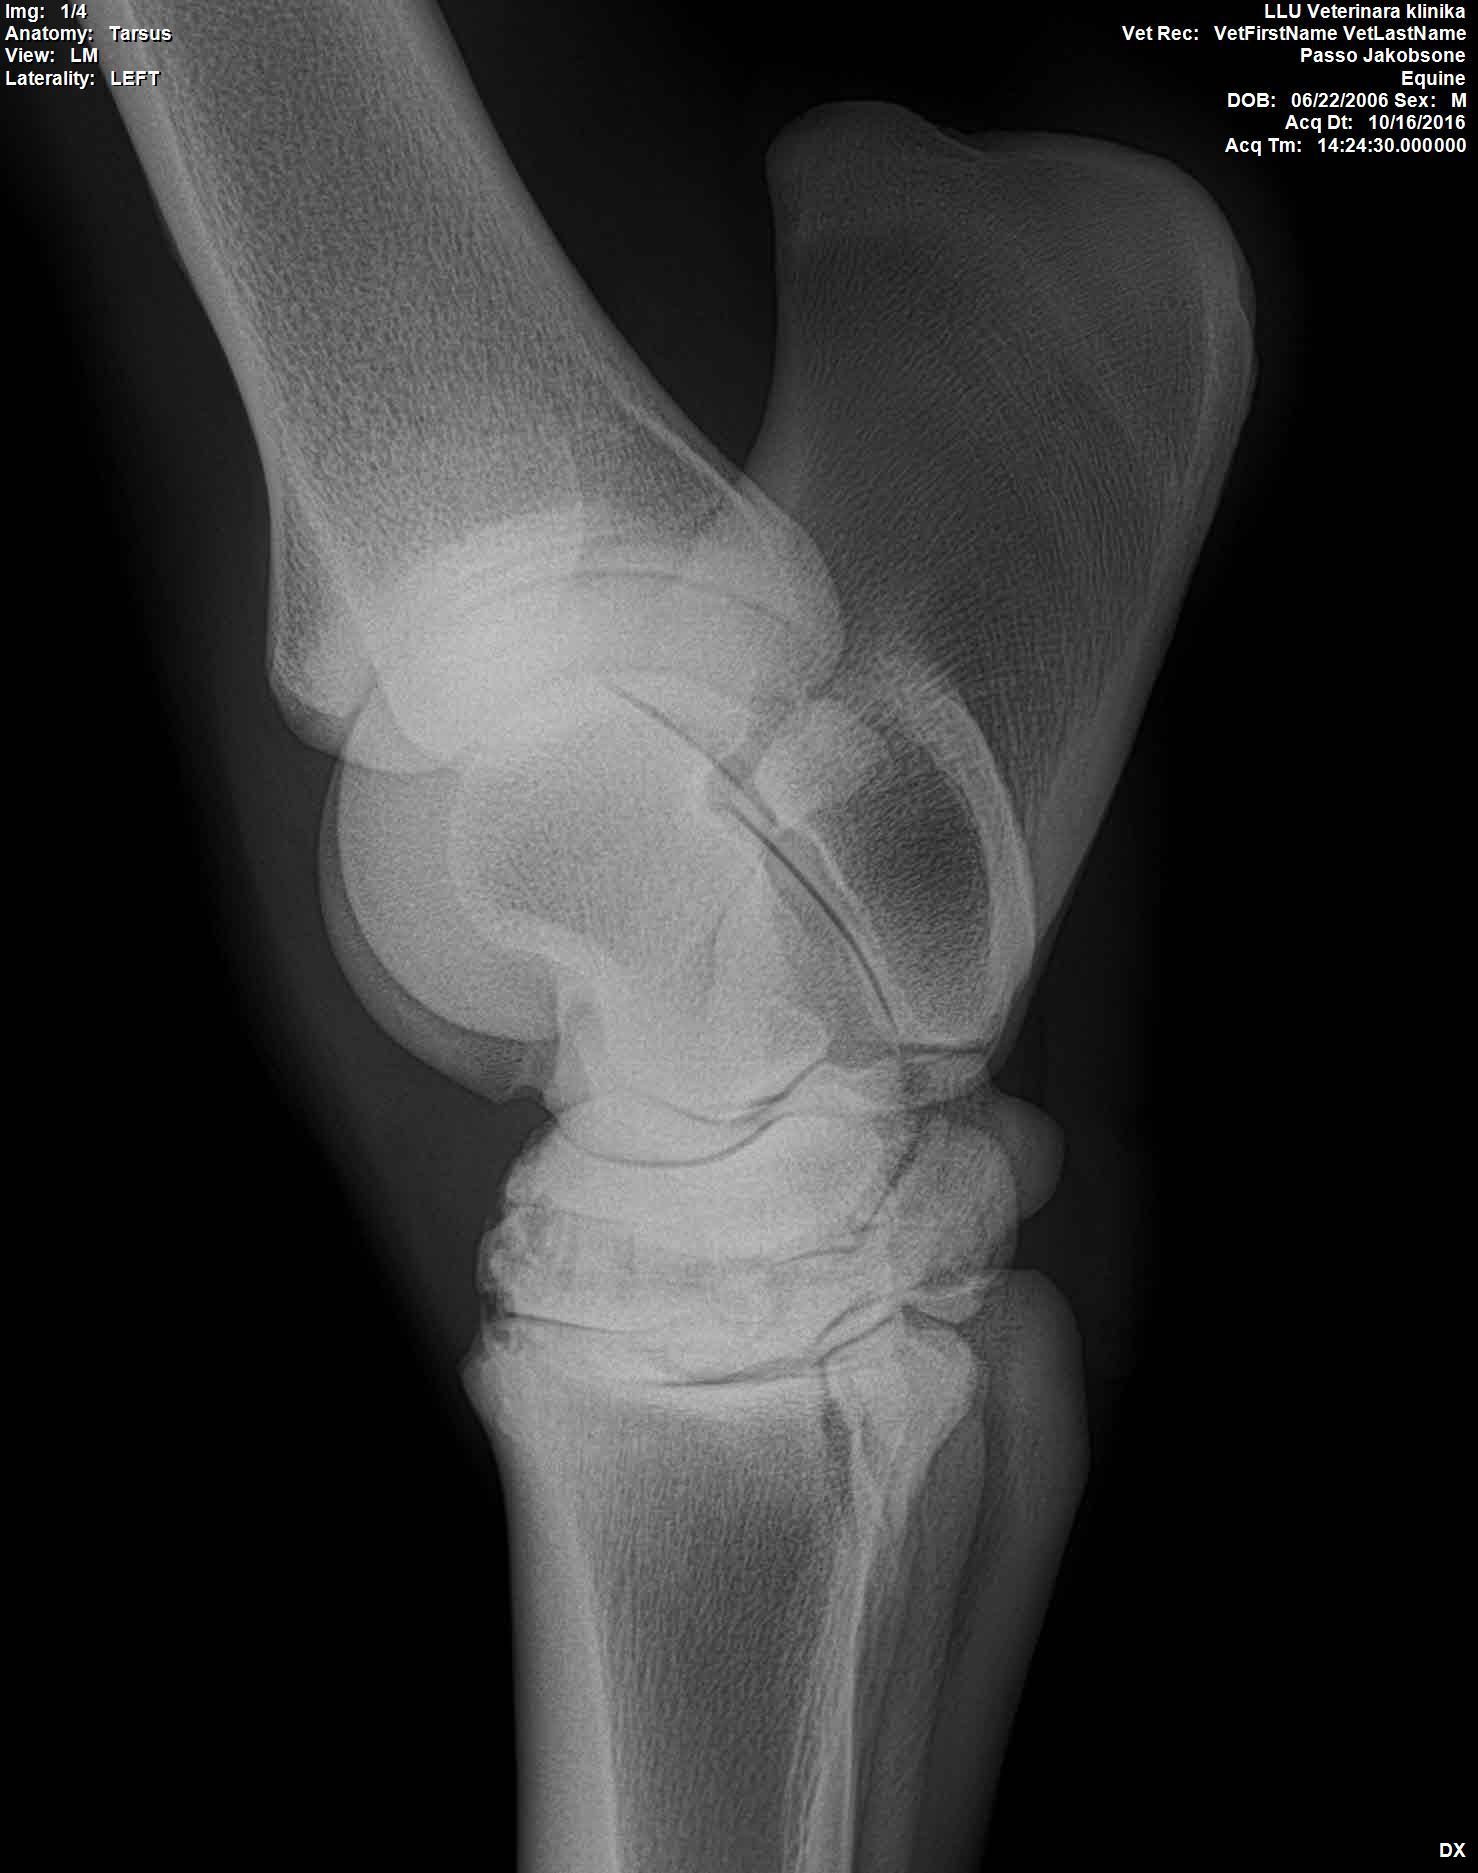

U majei loshadi ( 10 let) kastrat, v proslom godu obnaruzili spat I sdelali kurss Tildren, 16.10.2017. ehso odin kurss, daju polgoda eto http://ru.eggersmann.info/432_/132_Profi_Gelenk_aktiv.html, I vot kakije u loshadi rentgeni po datam. Prigaju do 110 cm, edu na sorevnavanije, idjot on horosho. esli stojal v bokse , snachala hromaet,no potom 2-4 minuti v risi i prohodit. Ja bi hotela prigatj vishe,no bojus ,mozno li. Letom dva raza bila ,chto v trenirovke zahramal ochen silno,no cerez paru chasov ,vsjo proslo.